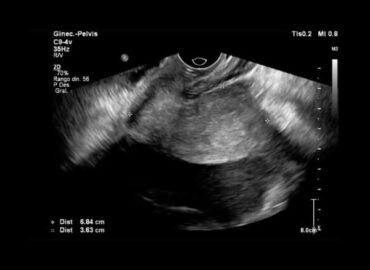

Paciente femenina de 20 años, sin APP, consulta por dolor abdominal agudo.